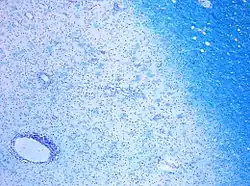

![]() | |

| CD68-stained tissue shows several macrophages in the area of a demyelinated lesion caused by MS. | |